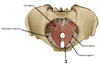

Where are the 3 potential sites of obstruction of the ureters in case of kidney stones?

- at the junction of the ureters and the renal pelvis

- where the ureters cross the brim of the pelvic inlet

- during their passage through the wall of the bladder